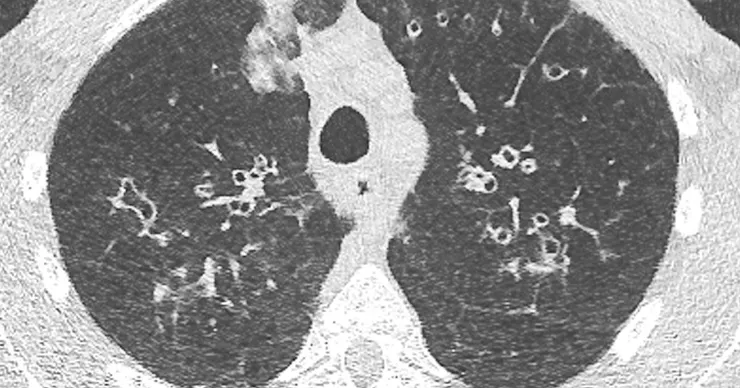

答案就是:低劑量電腦斷層掃描(LDCT, Low dose CT)。

Ultra-low dose CT chest | Radiology SA